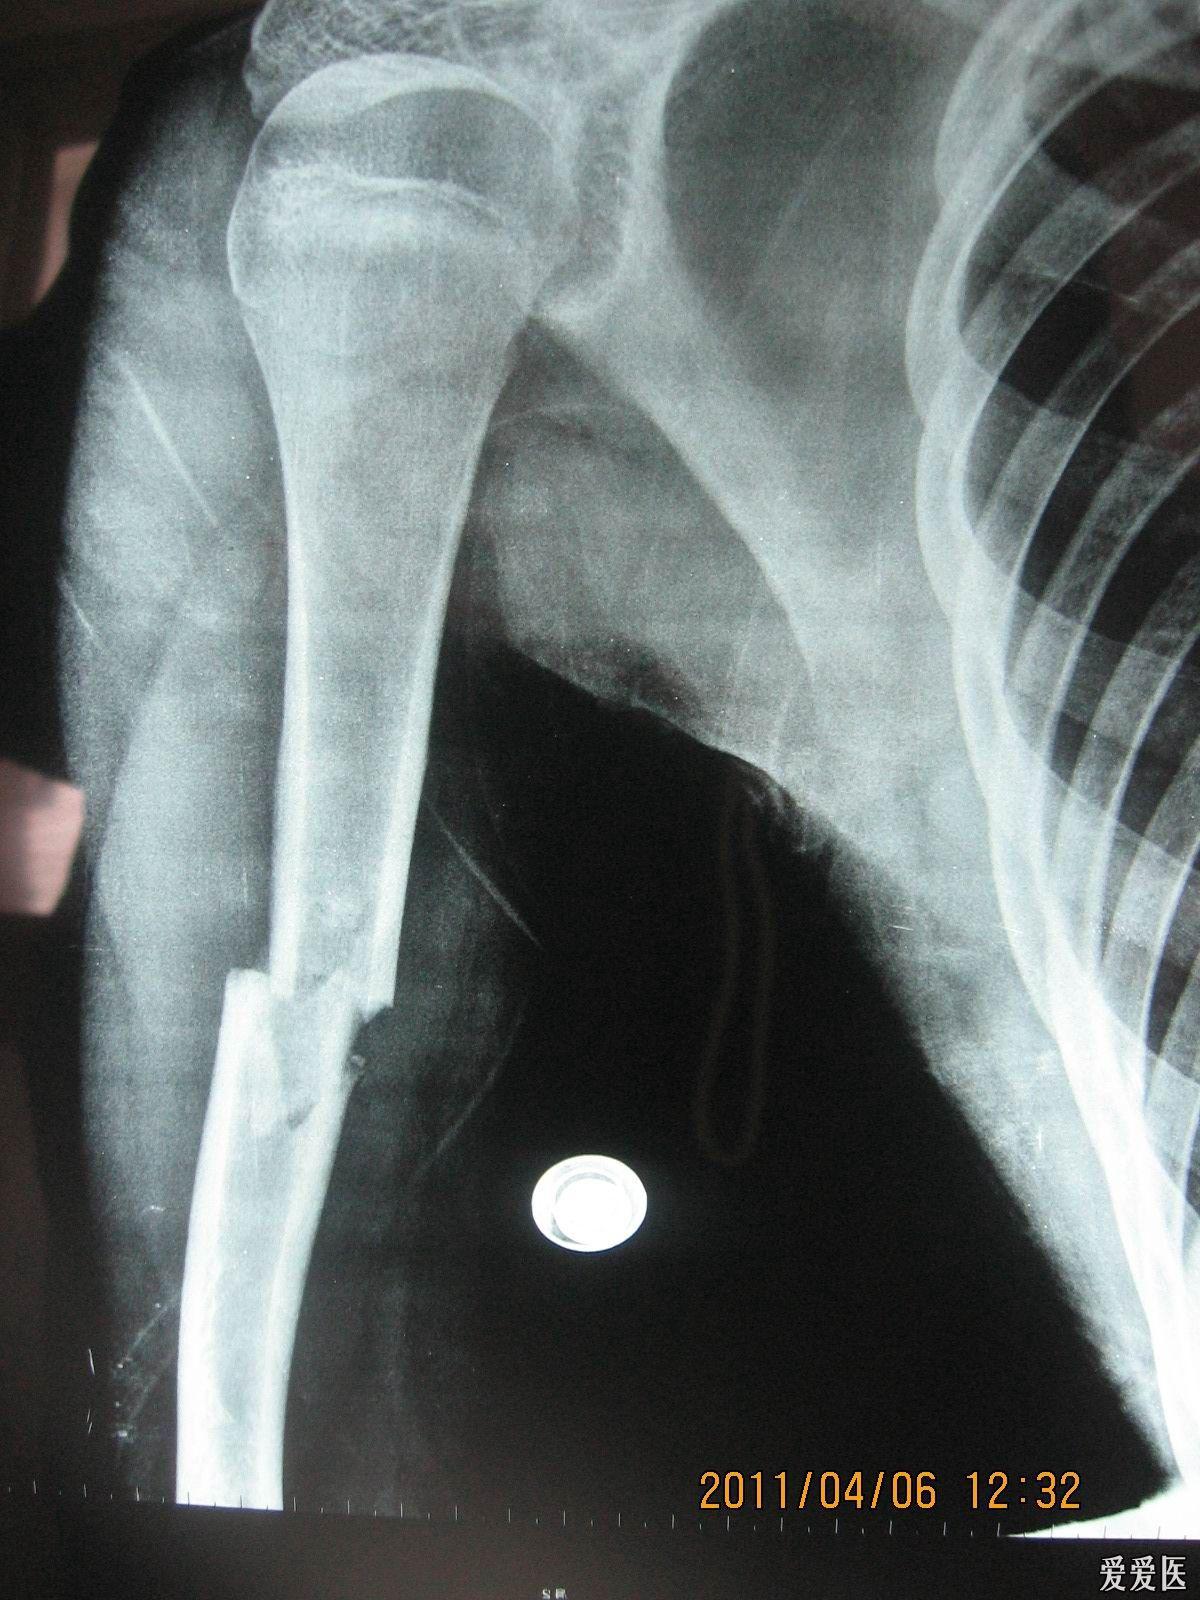

孩子摔伤,左肱骨近端骨折,是保守治疗还是动手术治疗好

图片尺寸640x1387